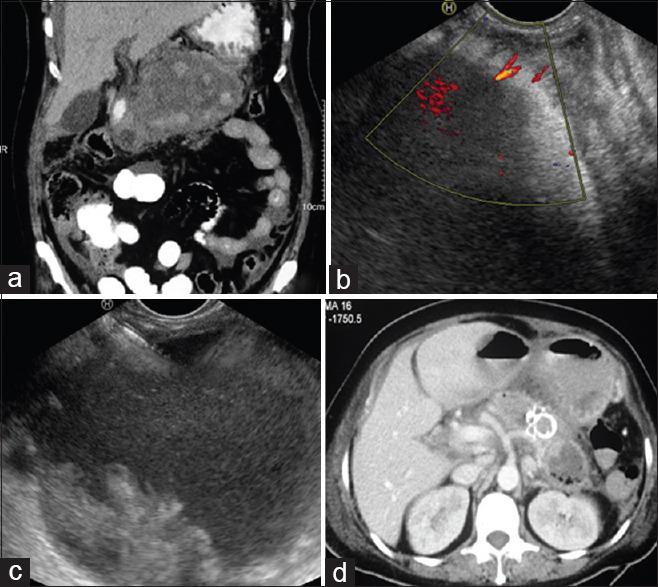

EUS-guided transmural drainage of hemorrhagic pancreatic fluid collections without associated arterial pseudoaneurysms.

https://cdn.ncbi.nlm.nih.gov/pmc/blobs/22b8/8544005/f48a71378eeb/EUS-10-396-g001.jpg